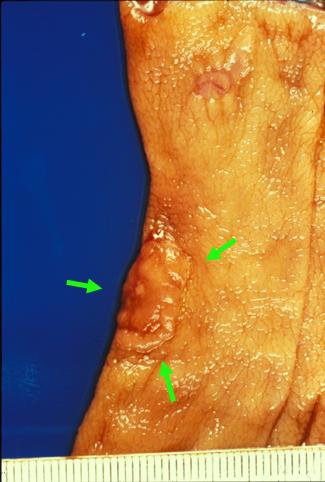

질환(병리주체)의 분류 악성 상피성종양/선암

부위(장기별) 대장/직장

검사방법 마크로

종양의 육안분류 0형(표재형)/IIa형(IIa)

종양의 최대경(밀리미터) 10~14

종양의 심달도 sm